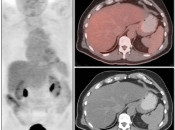

The normal liver demonstrates diffuse FDG uptake (typically greater than or equal to the spleen).

Many readers consider the uptake in the liver to represent the “background metabolic activity” for an exam.

For assessment of many lesions found in the body, the metabolic activity of the liver serves as the reference threshold by which to decide what is benign (uptake < liver) and what is malignant (uptake > liver).

Focal increased FDG uptake in the liver is always highly suspicious for malignancy. Very commonly, these malignant lesions may be poorly delineated on the co-registered CT images due to the lack of intravenous contrast administration.

Non-avid, low attenuation liver lesions are almost always benign (usually representing cysts, hemangiomas or fully treated malignant lesions), although some hepatocellular carcinomas can demonstrate only very mild metabolic activity.